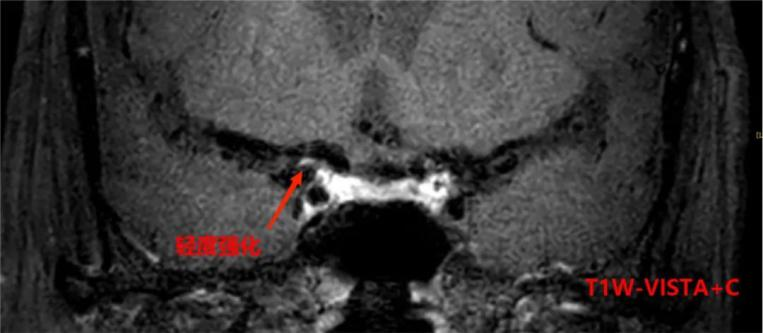

以上4图平扫的T1W-VISTAT2WT1W-3D-SNAP都发现大脑中动脉M1段的大小为1.2*1.5*2.8mm等低信号斑块。

6c7180e7ed935be81a1d0dac685b2bb3.pngf8d20e7e820aa9111b30f3e48b62d51c.png

上图是打药后扫描的T1W-VISTA+C图像,斑块表现为轻度强化,综合考虑为不稳定斑块。这种情况需要慎重处理,斑块破裂和脱落风险比较大,建议经药物治疗后随访复查。